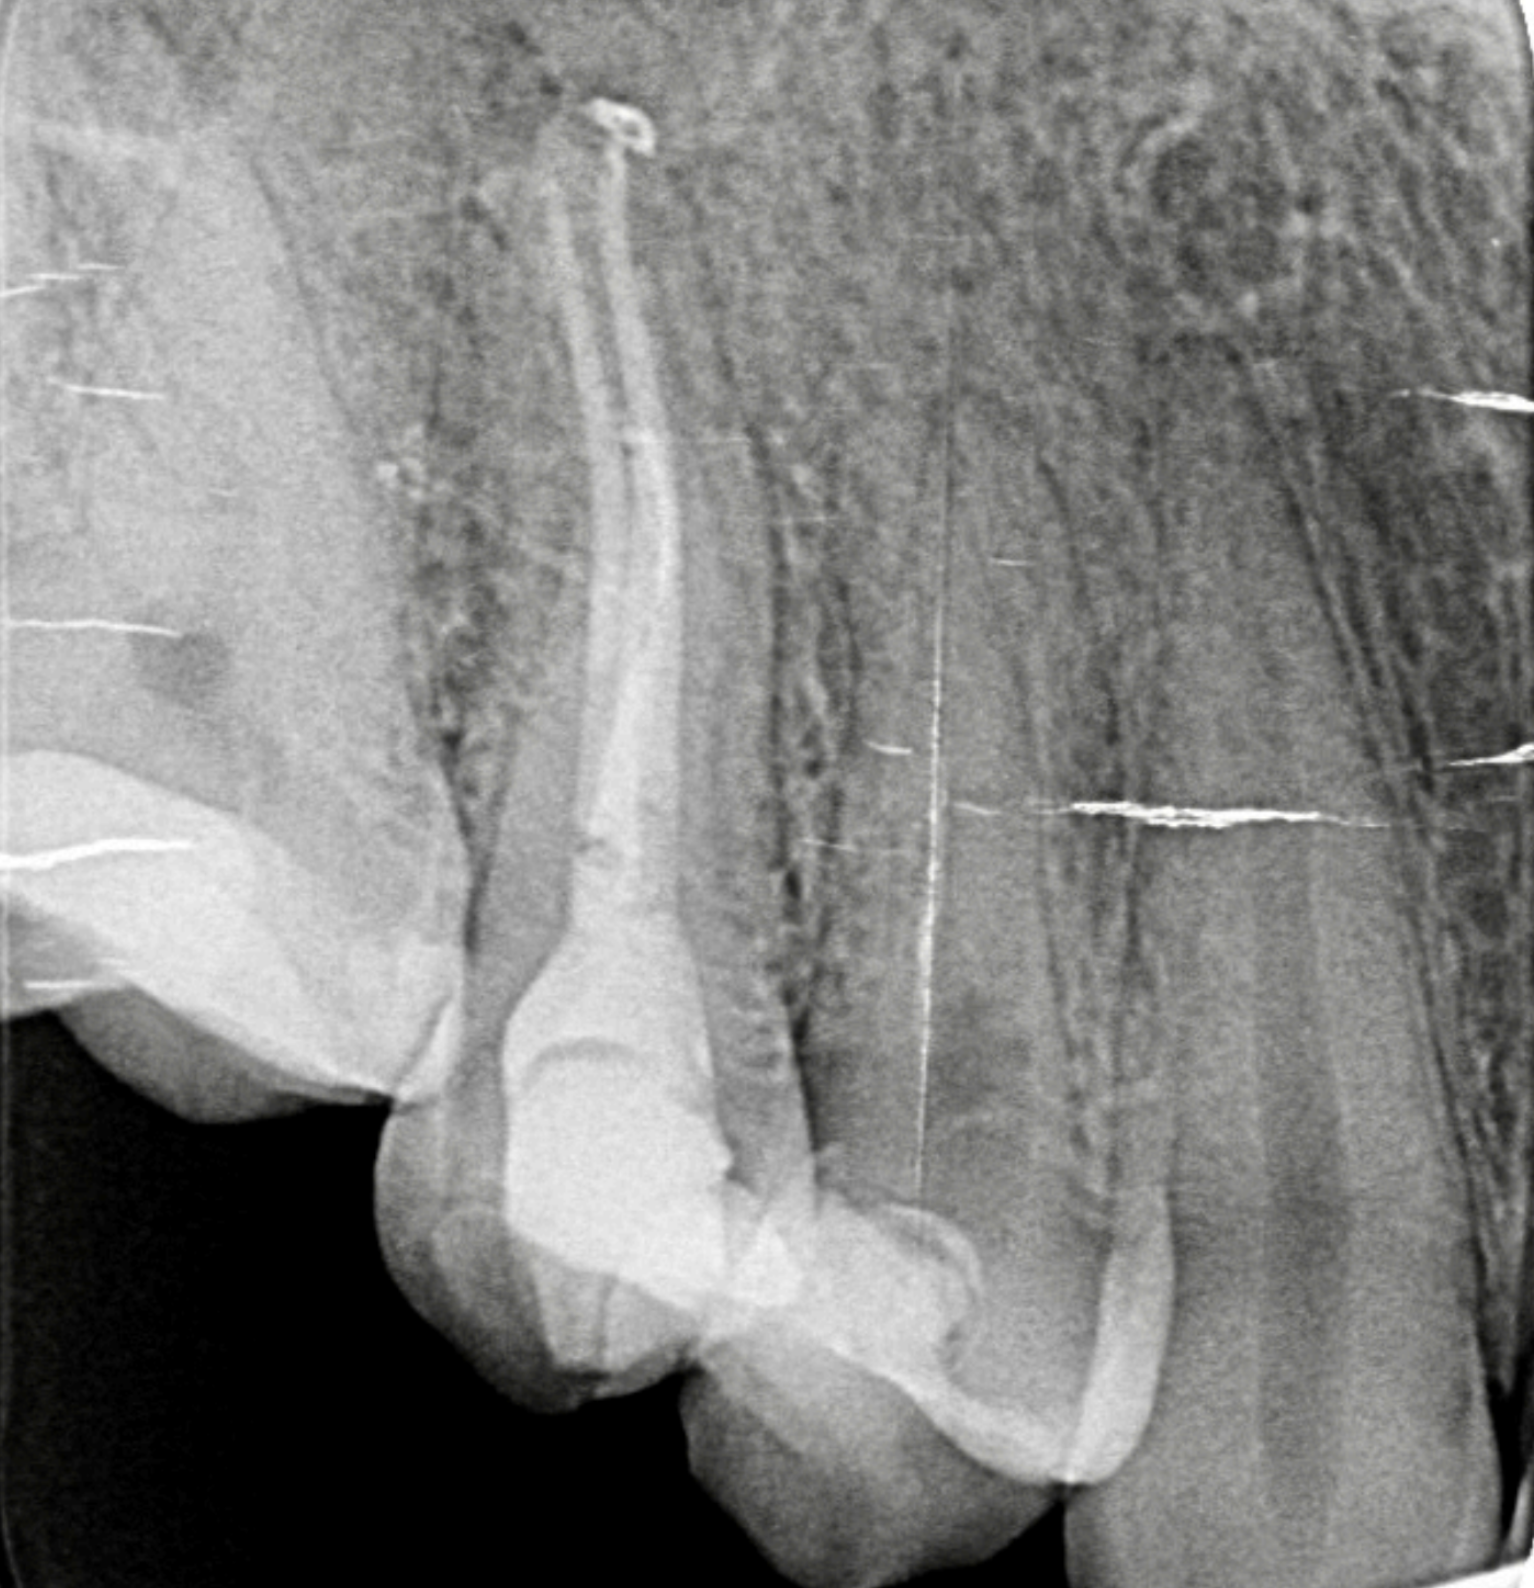

Aspectul pe radiografie al conului de gutaperca este alb (radioopac). El ar trebui sa umple in totalitate lungimea canalului si latimea lui. Acesta este un prim factor care asigura succesul tratamentului endodontic.

Retratament realizat prin curatarea si obturarea ambeleor canale ale premolarului superior